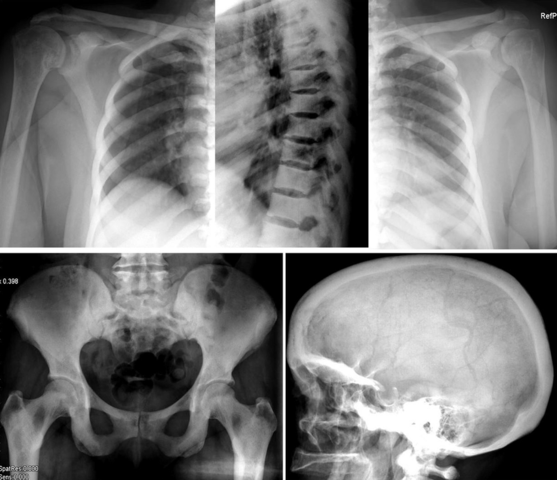

Equipos

EN 2020 Y 2021 el uso de los rayos x para la detención de las enfermedades atraves de los equipos como los razonadores , tomógrafos, y mamógrafos entre otros siempre dejando aun lado siempre los estigmas antiguos